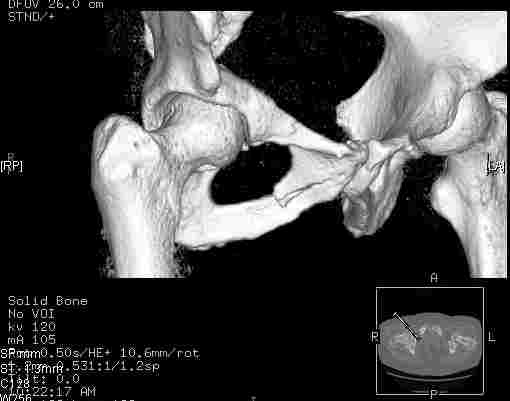

Удалось сегодня вывести пациентку в соседнюю больницу, где есть кт. Срезы сделаны только горизонтальные.

Следом 3d

Приветствую,Антон.Рункова рядом нет,но после полученных данных КТ,обсуждали совместно.Итог обсуждения-развернутый ответ дать не получится,т.к.срезы выбраны не информативные.Если ориентироваться на данные 3D,то ,ИМХО,можно лечить на вытяжении.